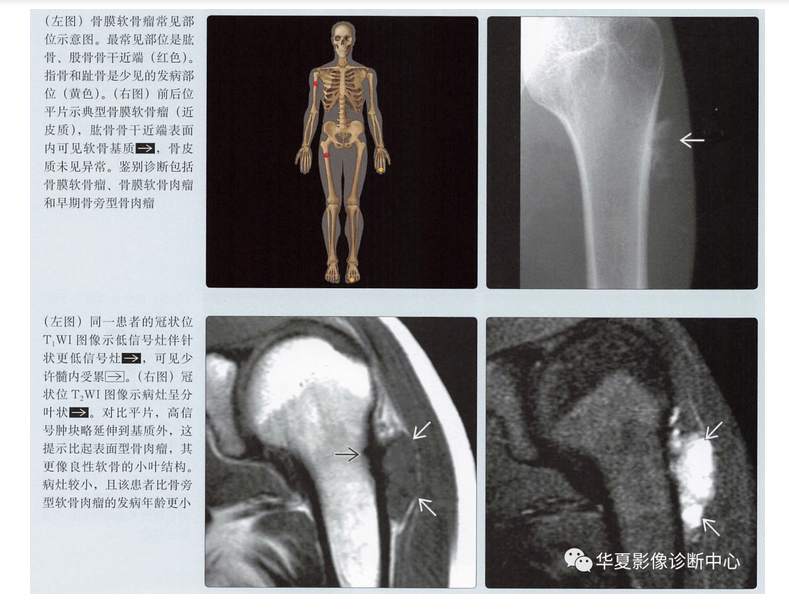

- 发病部位

- 干骺端,源于骨表面

- 肱骨或股骨近端(70%)

- 指骨或趾骨(25%)(手>足)

- 平片可以提示本病的诊断,并进行鉴别诊断

平片表现

- 骨皮质扇形凹陷

- 硬化边

- 致密性骨膜反应,尤其是在病灶近端、远端

- 病灶远端、近端骨皮质杯状改变

- 基质钙化(75%)

- 软组织肿块